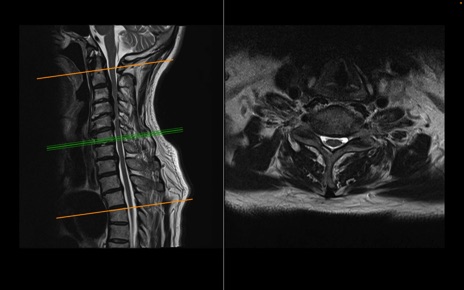

頚椎MRI

T2WI(横断像)

T2WI(矢状断像)